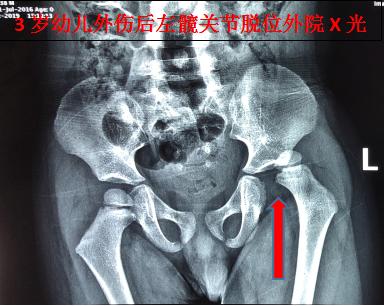

10月3日下午14时许,在随家长探亲途中,由于父亲疲劳驾驶致车辆失控撞树,3岁男童没有坐安全座椅,被重重地甩到车辆前座。孩子事后一直哭闹不止。经家长初步检查发现,其左下肢畸形不能活动,即被送至南沙区某医院急诊就诊,经该医院影像科X光片检查提示:左侧髋关节脱位。随即建议办理入院手术治疗。

骨伤六科副主任中医师陈凯奇当时正在休假,接到该患儿外伤病例电话邀诊后,立即组织该团队主治医师陈宏慈和医护人员启动假日接诊预案,进入相关接诊诊疗工作程序。患儿16时45分送达骨伤六科诊室,当时烦躁、哭闹不止。医疗团队快速、专业地开展诊治流程,经检查发现,幼儿左下肢短缩、屈曲、内收、内旋畸形,弹性固定,活动受限,于患侧髋臀肌部可触及隆起。再详细查阅外院X光片,结合幼儿遭遇外力撞击的情况,确诊为:左髋关节脱位(后脱位)。

经过2分钟的中医正骨手法治疗后,下午17时35分,患儿复查X光检查结果出来了,骨伤六科医疗团队看到幼儿左髋关节脱位复位后关节位置结构正常,如释重负地松了一口气。